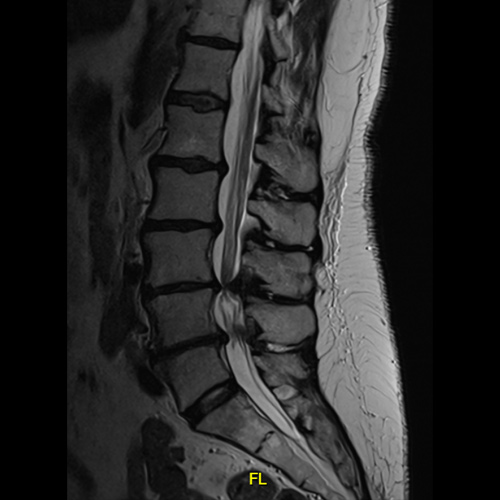

Spinal stenosis (Lumbar) Spinal stenosis (Cervical) Spinal stenosis (Thoracic) Lumbar Disc Herniation Spondylolisthesis Cervical Foraminal Stenosis Vertebroplasty Lumbar Fusion Anterior Cervical Fusion (ACDF) Posterior Cervical Fusion Thoracic Fusion Revision Lumbar Fusion Surgery Facet Joint Cyst Spinal Tumour Minimally Invasive Lumbar Fusion (XLIF) Minimally Invasive Lumbar Fusion (ALIF) Lumbar Fusion (TLIF) Thoraco-lumbar Fusion Lumbar Corpectomy Complex Lumbar Spine Surgery (Spino-pelvic fixation) Complex Cervical Spine Surgery Complex Thoracic Spine Surgery Occipito-cervical Fusion Minimally invasive surgery for thoracic disc herniation Other Related Topics